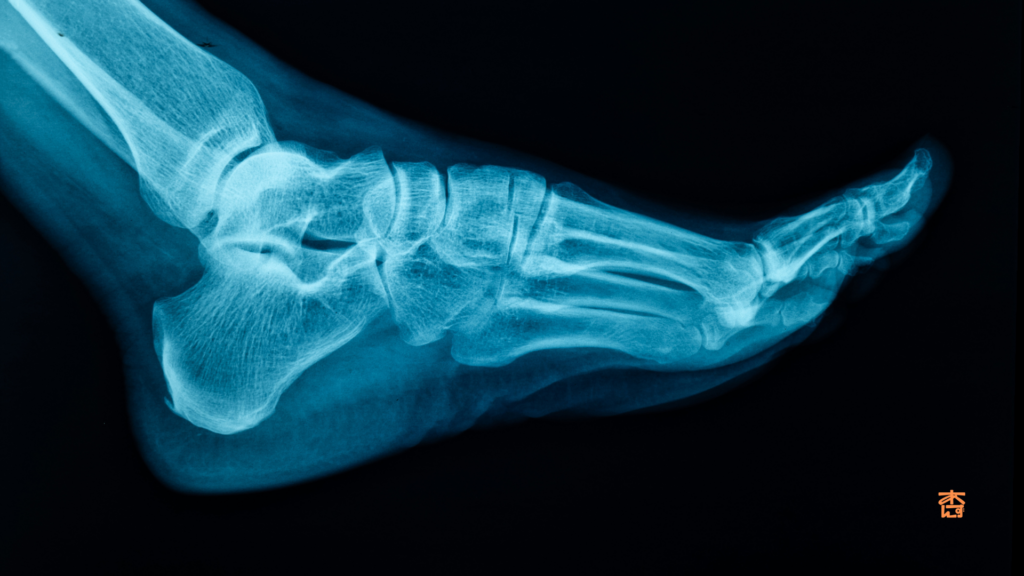

腓骨下端骨折とは?

腓骨ってどこの骨?

腓骨はすねにある二本の骨のうち外側(小指側)にある細い骨のことです。

足首に近い部分(下端)は特に骨折しやすい場所として知られています。

転倒したときや足首を強くひねったときなどに折れてしまうことが多いんですね。

特にスポーツをされる方や高齢の方に多く見られる骨折です。